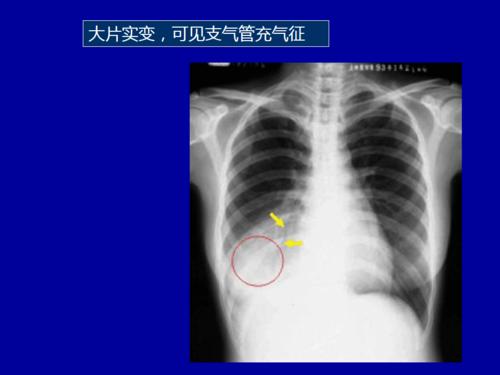

肺部大片阴影影像诊断

图22 或表现为网格状阴影,少数不典型的患者表现为弥漫性磨玻璃阴影.